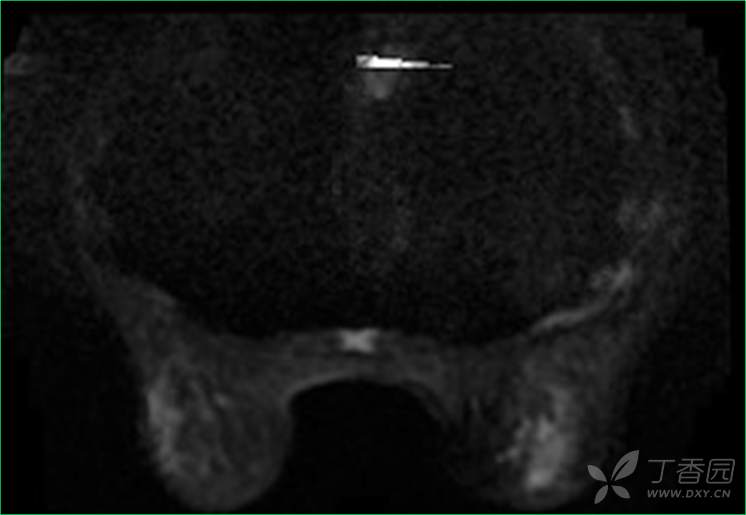

DWI

乳腺MR:左乳外上象限见T2WI高信号肿块影,大小约12mm×10mm×13mm,肿块为卵圆形,边缘模糊不规则;内部强化略不均匀;TIC曲线初始相呈快速强化,延迟期呈平台型;DWI呈高信号,ADC值为 0.000698 mm2/s。

因肿块边缘不规则,内部强化不均匀, TIC曲线初始相呈快速强化,延迟期呈平台型;DWI呈高信号,ADC值较低,考虑左乳外上象限肿块恶性不除外,BIRADS 4类。